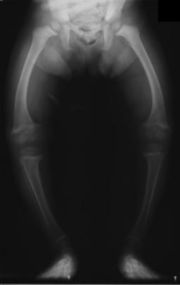

Křivice neboli rachitida (rachitis) je onemocnění dětí, vyvolané nedostatkem vitaminu D. Bývá způsobena nedostatečnou výživou, chudou na tento vitamin, ale také nedostatkem slunečního záření, jehož pomocí dovede tělo tvořit z některých látek vitamin.

Tato choroba se projevuje těžkou poruchou tvorby kostí - kosti měknou, převažuje chrupavčitá hmota. Zatímco ve zdravé kostní tkáni je chrupavčité složky asi 30%, v rachitické kosti až 70%. Ubývá značně fosforečných solí, kdežto obsah vápenatých solí se celkem nemění. Kostní změny mají za následek, že dochází k poruchám ve tvaru kostí. U kojence měknou kosti lebeční, zvláště týlní. Zuby rostou nepravidelně a jsou na kousacích plochách zoubkované, tvrdé patro je vysoko klenuté. Na žebrech je přechod části chrupavčité v kostní značně ztluštělý a tvoří tzv. rachitický růženec. I na ostatních kostech jsou hranice chrupavky a kosti zduřelé, kosti dolních končetin se ohýbají, dítě přestává chodit. Také obratle se hroutí a tím vznikají různé zkřiveniny páteře.